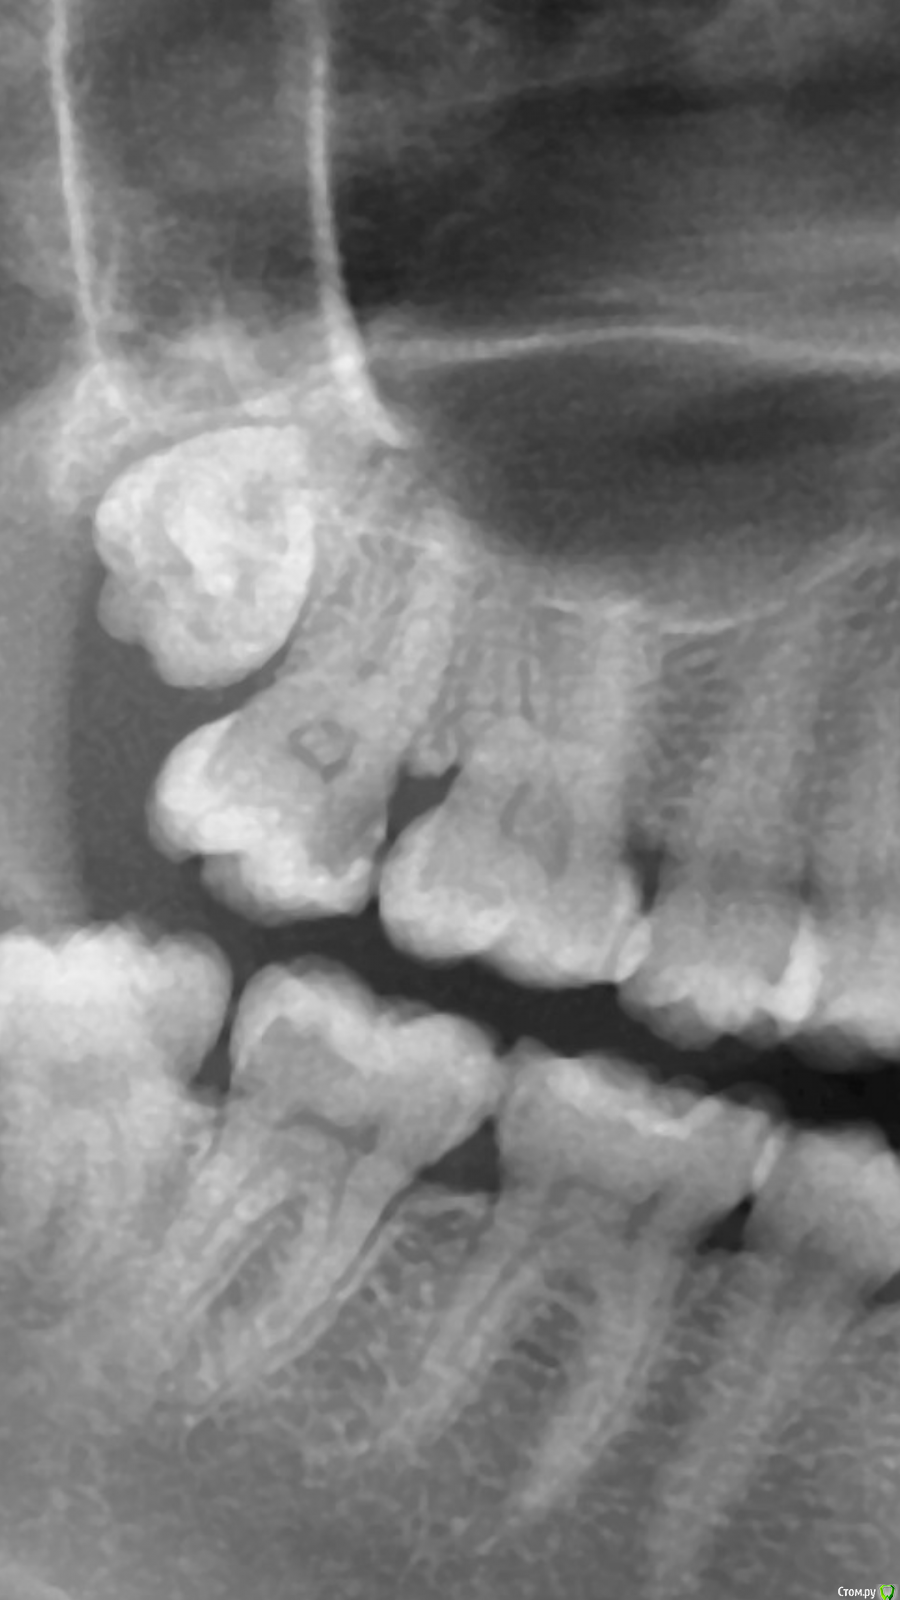

Malalejandra Опубликовано 1 февраля, 2017 Автор Поделиться Опубликовано 1 февраля, 2017 Спасибо, но, похоже, я немного сглупила, и сделала скриншот правой стороны панорамного снимка. Вот оба снимка, оба левые. Ссылка на комментарий

shishok Опубликовано 1 февраля, 2017 Поделиться Опубликовано 1 февраля, 2017 Я бы еще проверила нижние 6 и 8(6-лечить,8-проще удалить).На верхнем 7 кариес(как уже раньше сказали). Ссылка на комментарий

Malalejandra Опубликовано 1 февраля, 2017 Автор Поделиться Опубликовано 1 февраля, 2017 Я бы еще проверила нижние 6 и 8(6-лечить,8-проще удалить).На верхнем 7 кариес(как уже раньше сказали).Спасибо, 6ку уже вылечила. а 8ку удалить можно, если еще не до конца прорезались? Ссылка на комментарий